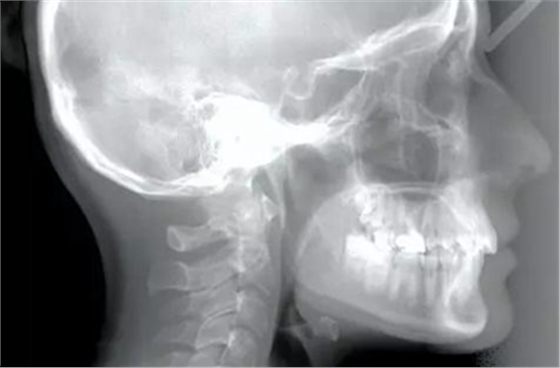

患者為19歲高加索女性,要求矯治中線不齊及上頜右側(cè)側(cè)切牙腭側(cè)異位。口內(nèi)檢查,左側(cè)安氏Ⅰ類尖牙、磨牙關(guān)系,右側(cè)安氏Ⅱ類尖牙、磨牙關(guān)系;上頜中線右偏4mm,下頜中線右偏2mm,16牙根管治療史,16及47有修復(fù)體;覆蓋5mm,覆合4mm,無(wú)橫向不調(diào)。功能檢查,顳下頜關(guān)節(jié)無(wú)明顯異常,面部及咀嚼肌不對(duì)稱。

頭影測(cè)量分析顯示,SNA為80.9°,SNB為79.5°,ANB為1.4°,SN-GoMe角為25.5°,下切牙到NA的角度為22°、距離為4mm,上頜切牙與NA角度為18°、距離為4mm,上唇在E線后5mm,下唇在E線后3mm,鼻唇角為110°。